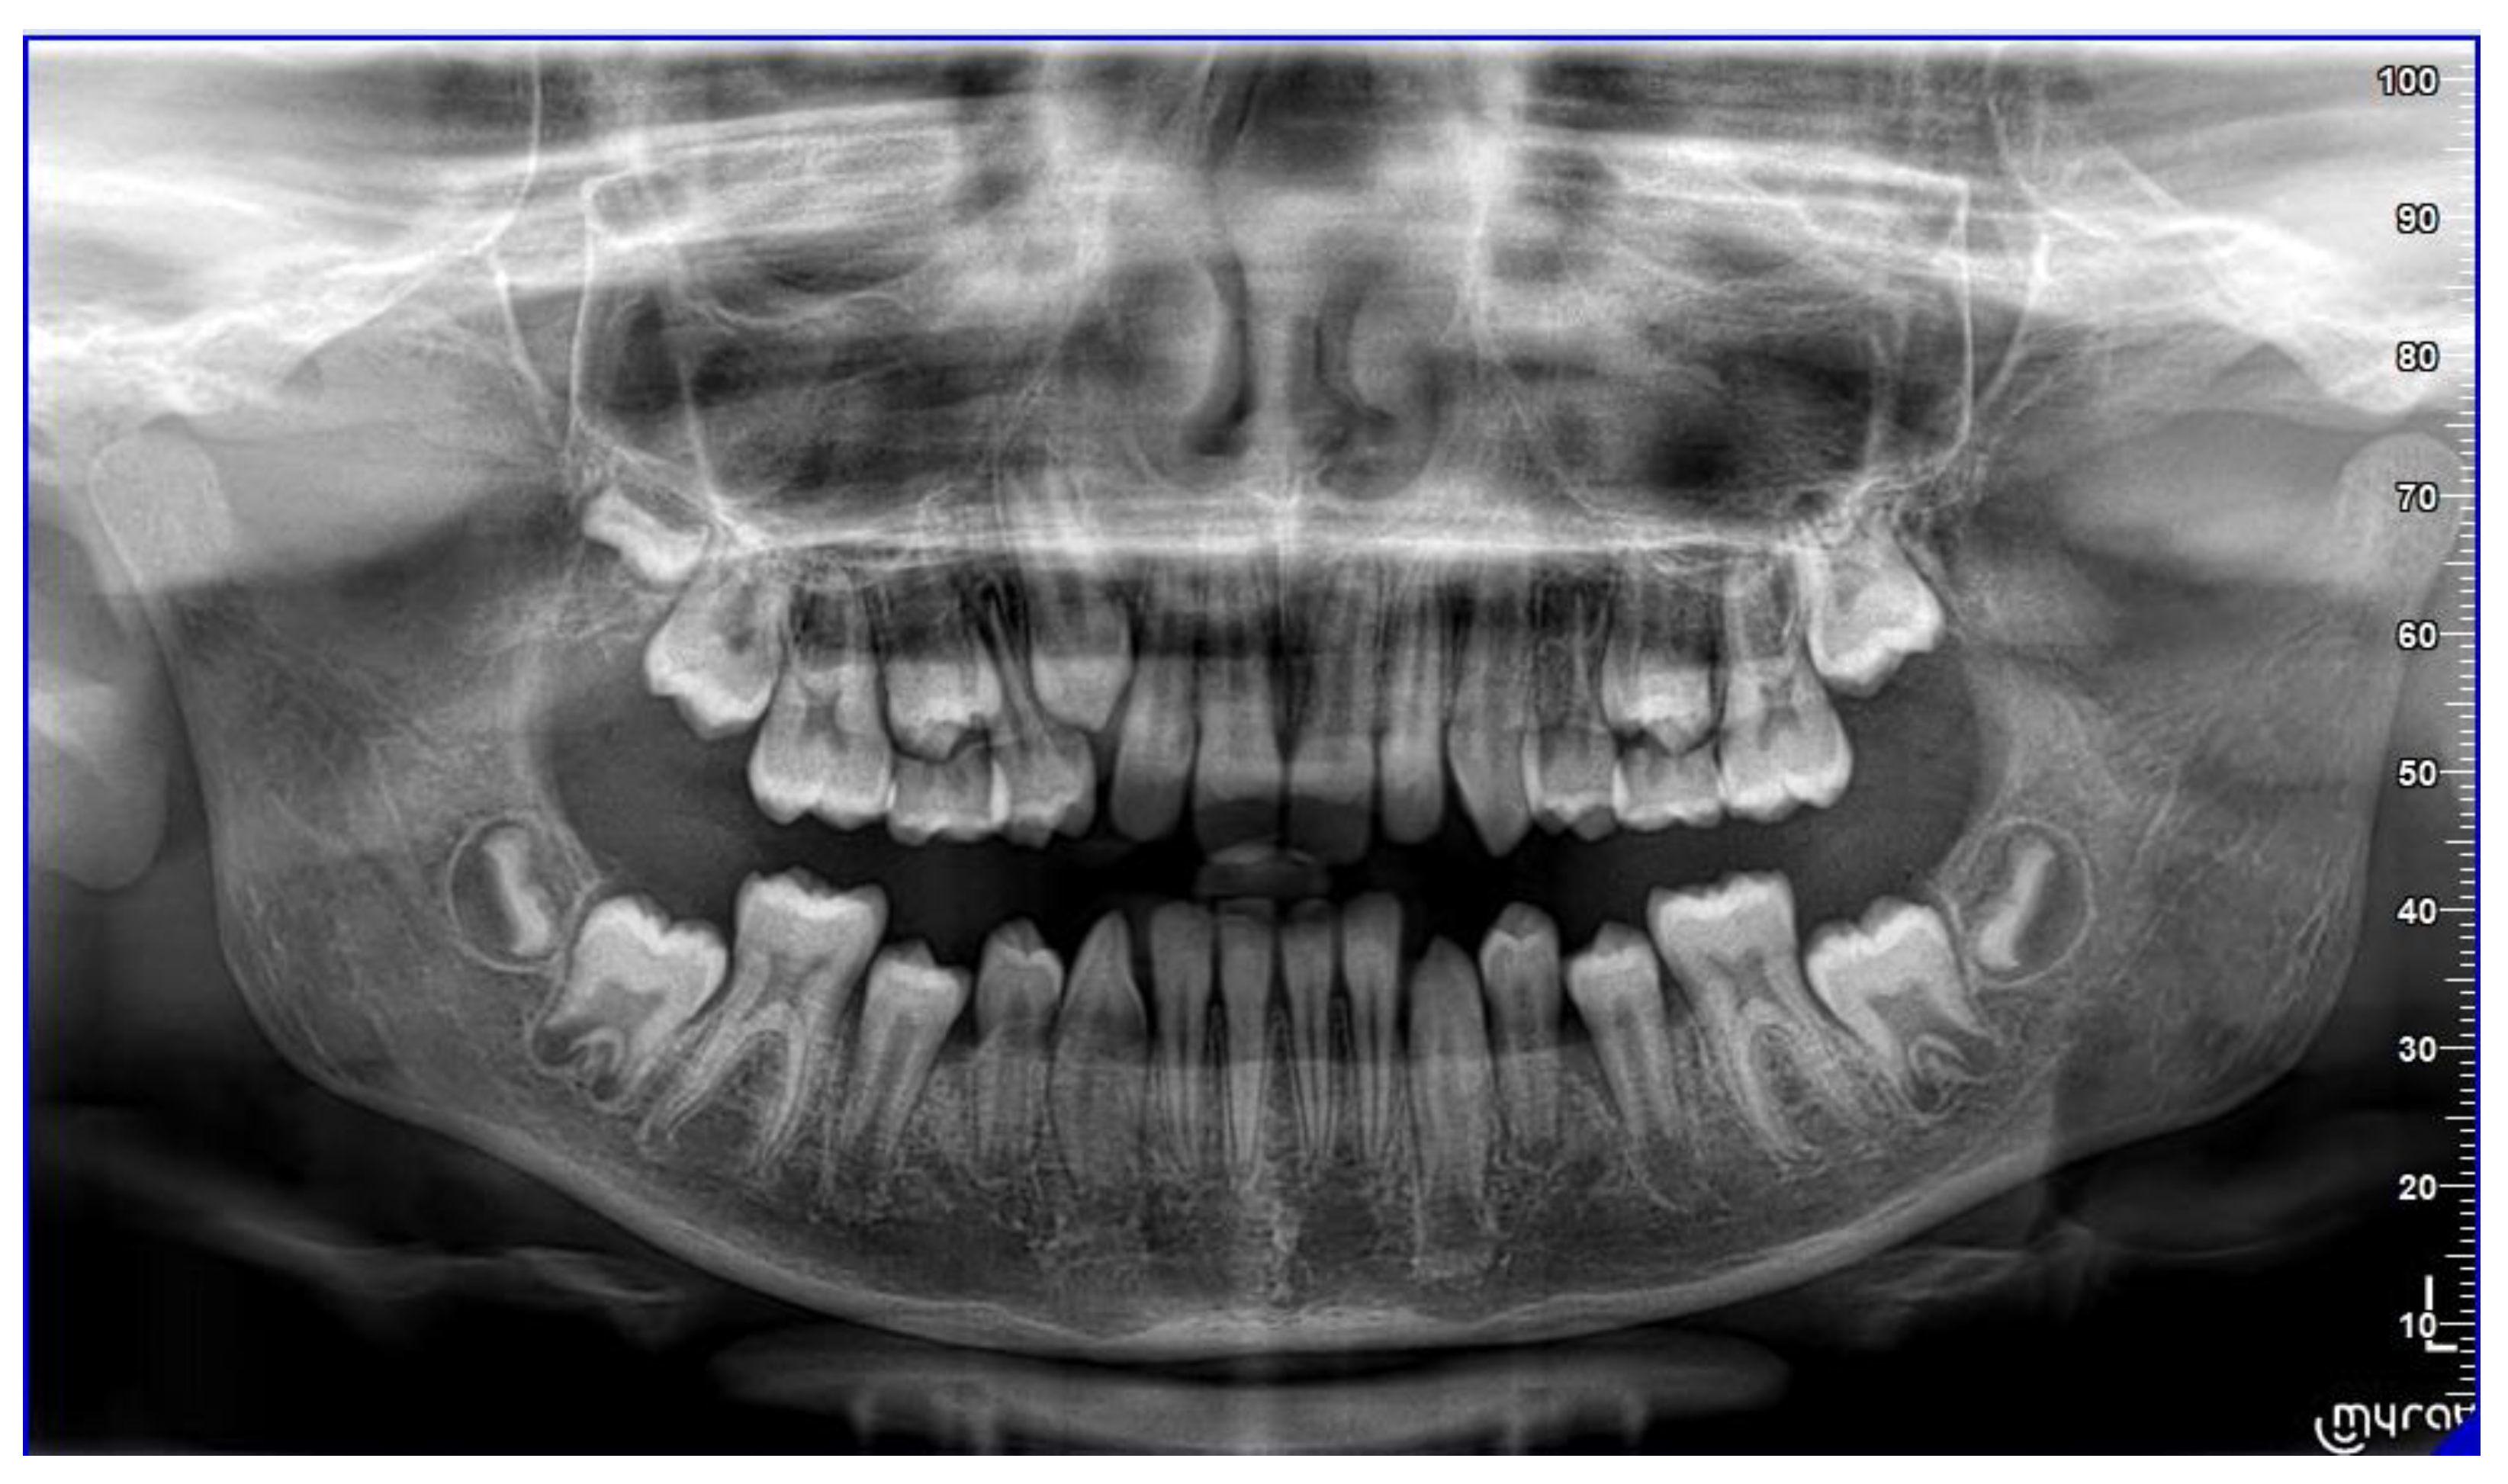

Case 2 concerns a 57-year-old male, with no systemic diseases. He came to our observation in November 2019, to carry out an orthodontic treatment to improve the esthetic appearance of his smile. He showed a good oral hygiene and periodontal condition. Intra-oral evaluation showed a reduction of the transverse diameters, both in the upper and lower dental arches, and a lack of space for the tooth 4.5 in the lower arch (Figure 9 and Figure 10). It was planned to re-establish elements 1.6 and 3.6 after orthodontic therapy in order to reach the first molar class. The most important problem for the patient was related to his smile esthetics and concerned the crossbite of the tooth 2.2.

Figure 9. Pre-treatment orthopantomography.

Sensors 21 01856 g009